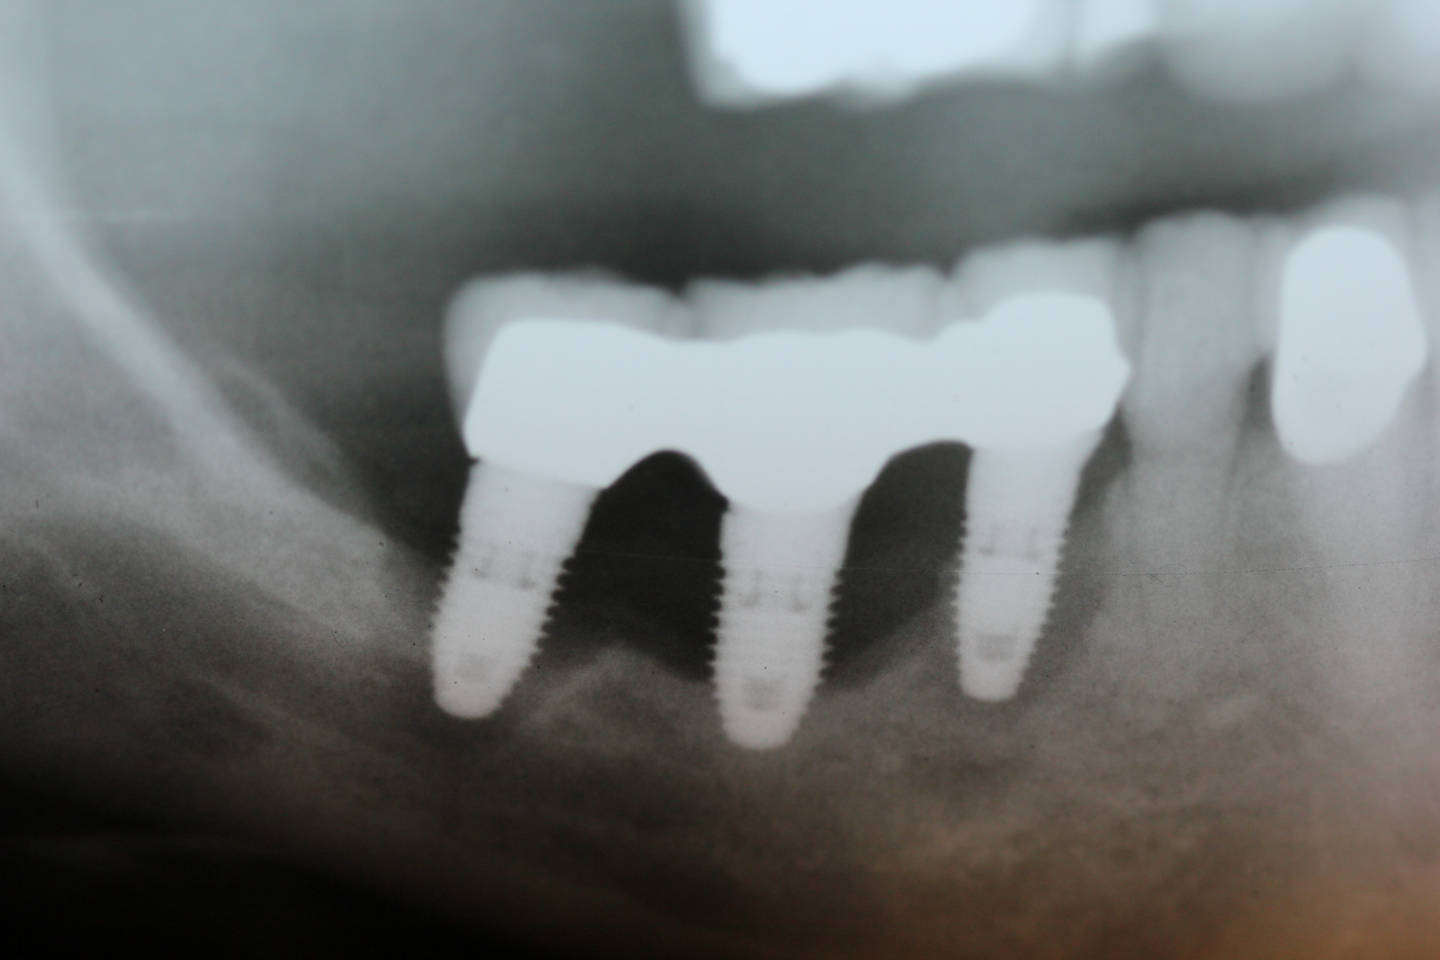

Fitting a new tooth. имплантация dentist Dental Clinic What Can Cause A Tooth Implant To Fail dental implant failure may occur early or late after the surgery. #1 misalignment of the implant: Healthy gums are a criteria for dental implant surgery, and you can’t have this procedure with active gum disease. a dental implant failure refers to the inability of the titanium screw of the implant to remain embedded firmly in the jawbone. It. What Can Cause A Tooth Implant To Fail.